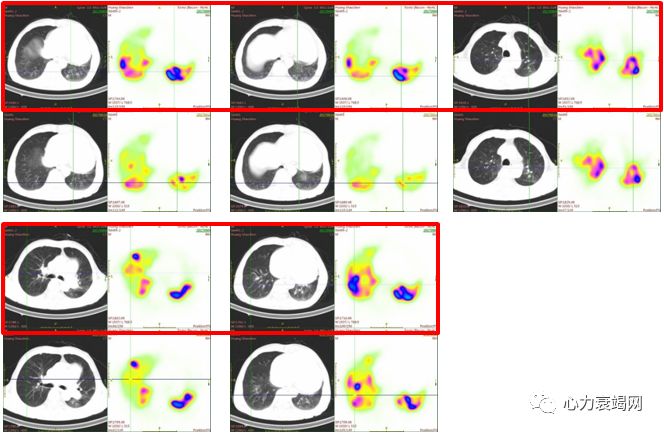

左肺下叶背段、右肺上叶前段、右肺下叶背段、右肺下叶基底段及右肺下叶外基底段通气/灌注显像不匹配

肺通气/灌注扫描:左肺上叶及下叶、右肺上叶、中叶及下叶肺栓塞高度可能

右肺上叶尖段、前段、后段、右肺中叶内侧和外侧段、右肺下叶背段和内外基底段、左肺上叶尖后段、前段、舌段、左肺下叶前内基底段、外基底段灌注改善

球囊扩张术后右肺上叶前段和后段、右肺中叶内侧段、左肺上叶尖后段和舌段、左肺下叶外基底段和后基底段肺灌注增加